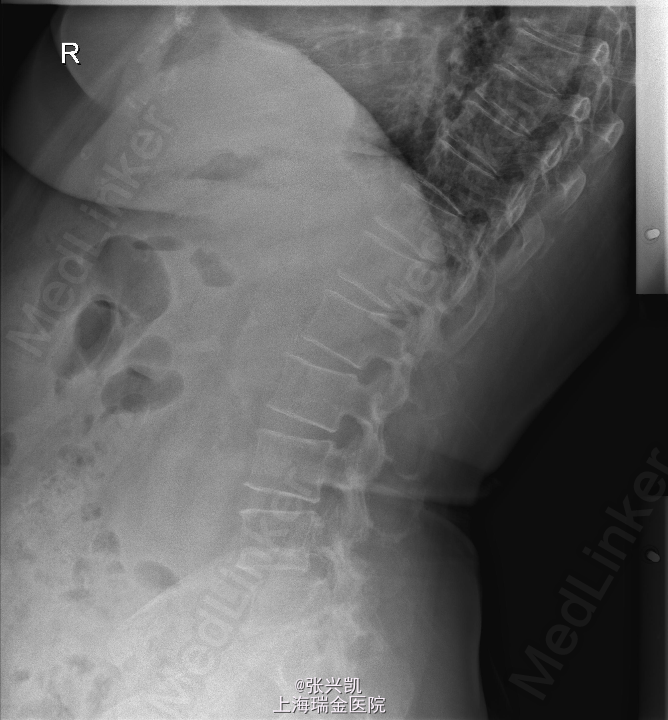

诊断:腰椎椎管狭窄L4-5 L4椎体滑脱 处理:腰椎后路减压复位融合内定术

随访:患者术后三月随访,下肢疼痛症状消失,可正常行走,腰部偶感酸胀感 讨论:针对术后有的患者有腰部酸胀不适感,有什么好的对症处理办法?